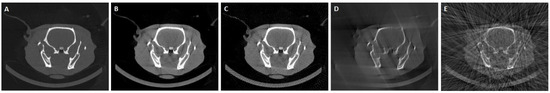

3.3. Results in Conventional Scenarios